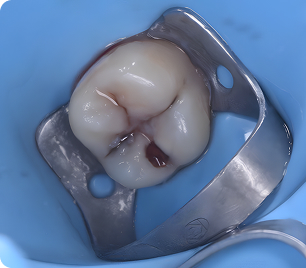

Бұрын

Бұрын